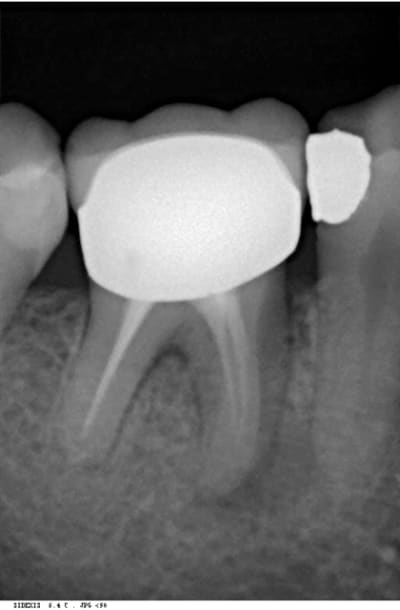

bon les pièces jointes d'alhoun.

décidément aussi nul en endo qu'en internet, et ton implant il est de traviole;)

Trev4 oye2tl - Eugenol

Trev5 lavbuq - Eugenol

Trev1 rgpu7x - Eugenol

Trev2 c5sddm - Eugenol

Trev3 wgcbda - Eugenol

dans la même philosophie de connectique

Easyimplant mjxotp - Eugenol

Rvg easy briwxo - Eugenol

çà doit être une déformation du cliché, regardes bien le premier cliché avec le pilier de cicatisation: on voit bien la partie cylindrique puis l'évasement.